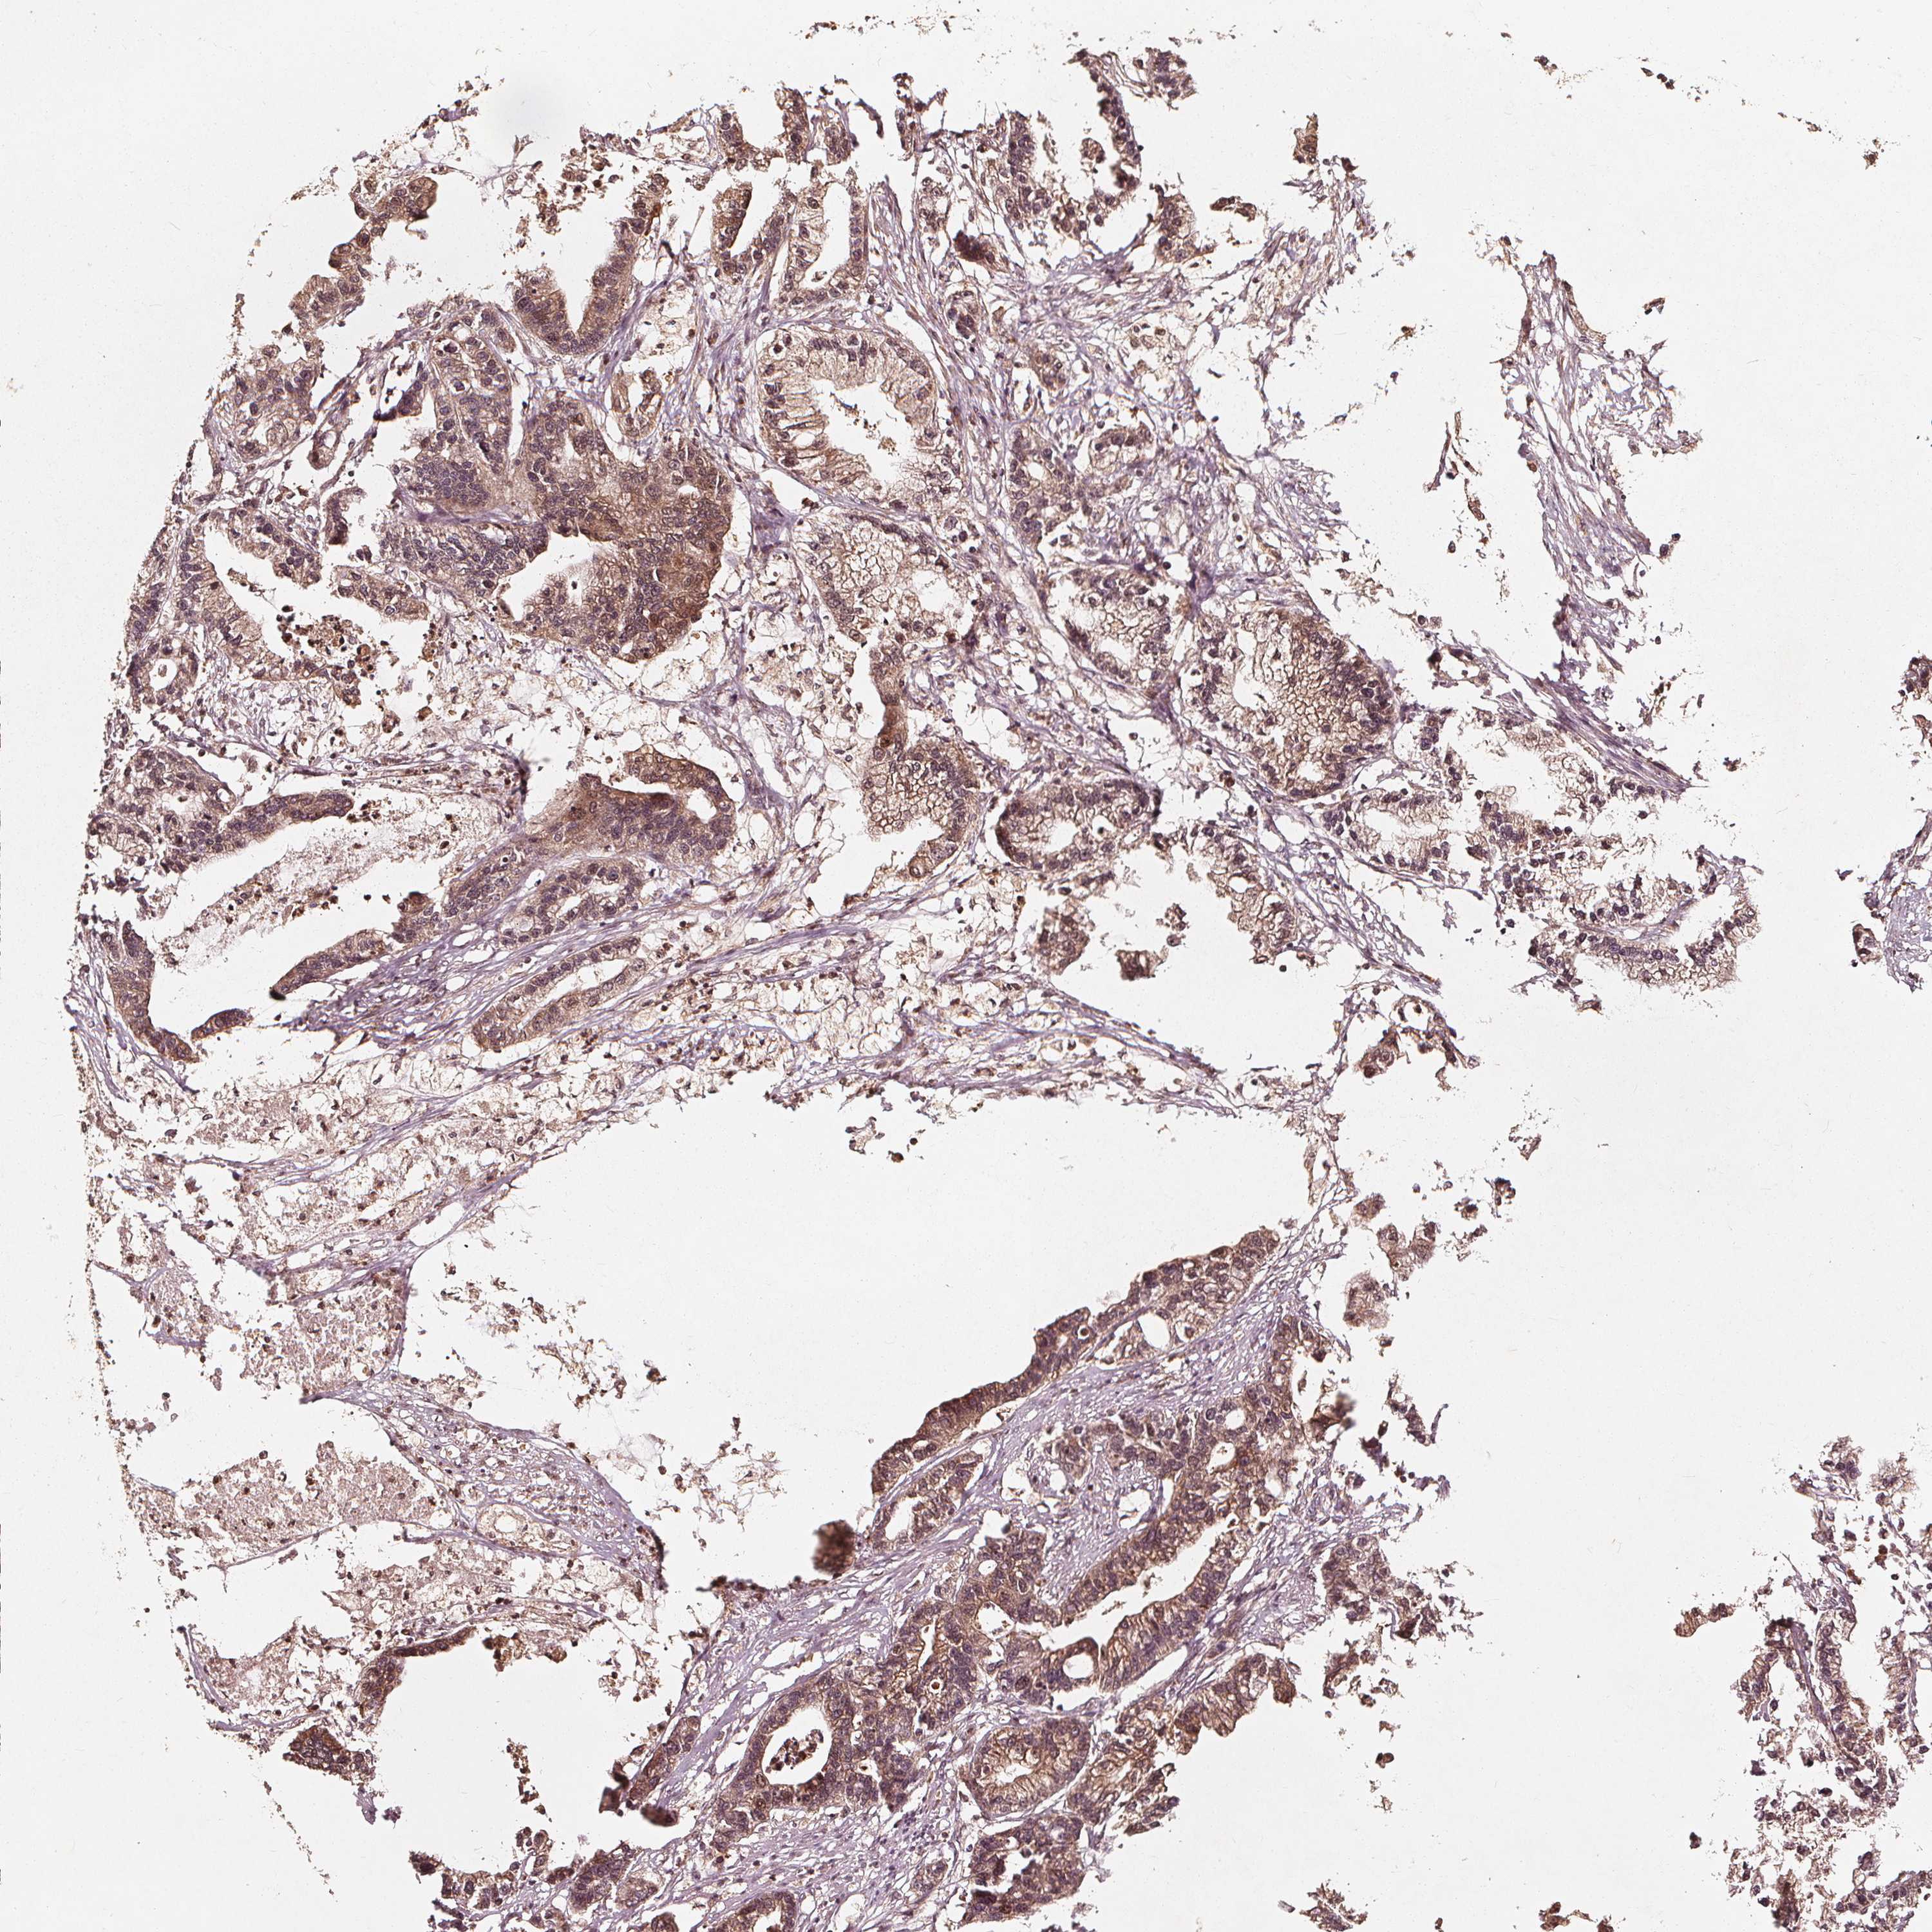

STOMACH CANCER - Protein expressioni

A mouse-over function shows sample information and annotation data. Click on an image to view it in a full screen mode. Samples can be filtered based on level of antibody staining by selecting one or several of the following categories: high, medium, low and not detected. The assay and annotation is described here.

Note that samples used for immunohistochemistry by the Human Protein Atlas do not correspond to samples in the TCGA dataset.

Antibody stainingi

Antibody staining in the annotated cell types in the current human tissue is reported as not detected, low, medium, or high, based on conventional immunohistochemistry profiling in selected tissues. This score is based on the combination of the staining intensity and fraction of stained cells.

Each image is clickable and will lead to virtual microscopy that enables deeper exploration of all samples and also displays staining intensity scores, fraction scores and subcellular localization as well as patient and tissue information for each sample.

Antibody HPA026618

Antibody CAB070132

Staining

High

Medium

Low

Not detected

Intensity

Strong

Moderate

Weak

Negative

Quantity

>75%

75%-25%

<25%

None

Location

Nuclear

Cytoplasmic/membranous

Cytoplasmic/membranous,nuclear

Adenocarcinoma, NOS